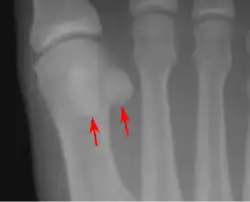

- One or both of the sesamoid bones under the first metatarsophalangeal joint (of the great toe) can be multipartite – in two or three parts (mostly bipartite – in two parts).[12]

Lateral view.[11]- Bipartite medial sesamoid bone under the first metatarsophalangeal joint of the great toe of the left foot of an adult woman.